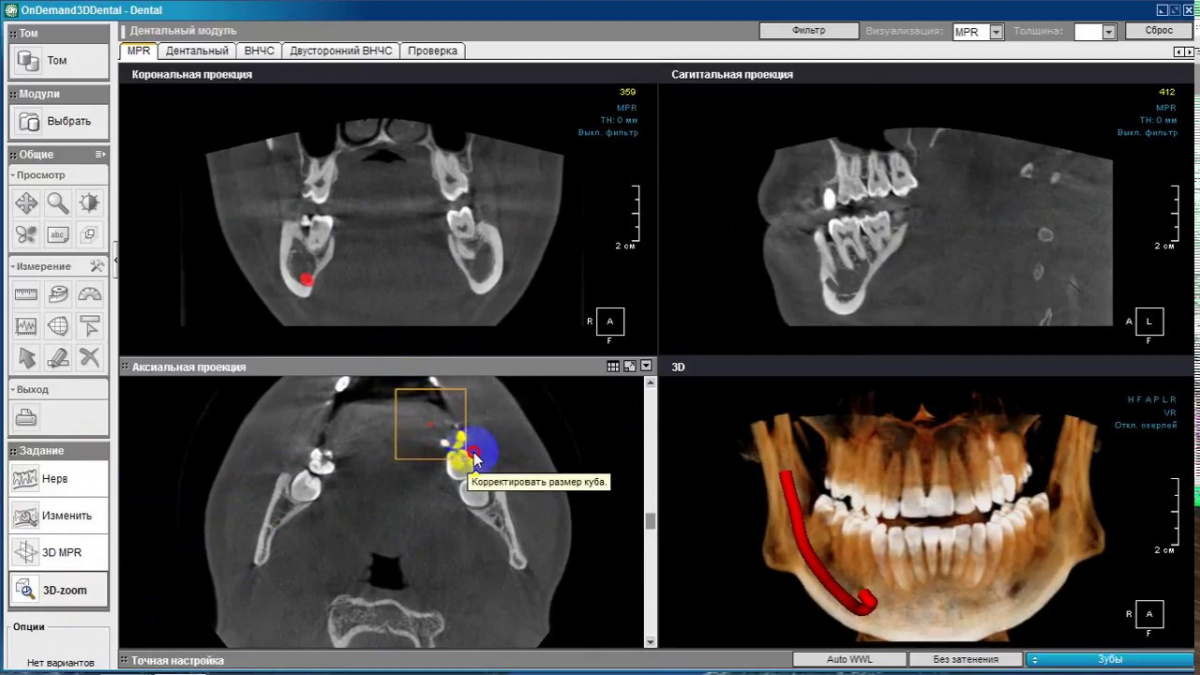

Немаловажным, а может главным вопросом, является универсальность программы-просмотровщика, в которой будут работать врачи-стоматологи. У Papaya 3D есть два варианта программ: Triana и OnDemand3D. Оба просмотровщика обладают схожим интерфейсом и имеют самые важные опции, а именно:

• режим MPR (многоплоскостная реконструкция). Именно здесь выстраивается интересующий участок челюсти или зуба для анализа.

• панорамный реформат. Возможность постройки классической и сегментарной панорамы позволяет продемонстрировать план лечения пациенту, а также оценить расположение анатомических структур на боковых кросс-секциях.

• модуль дентальной имплантации. Возможность виртуальной установки дентального имплантата с анализом окружающей костной ткани. В библиотеке представлен широкий спектр имплантологических систем с индивидуальной прорисовкой имплантата.

• выделение нижнечелюстного канала позволяет продемонстрировать расположение важного анатомического образования и определить зону безопасности при проведении лечения.

• функции плотности, линейных измерений и угла – необходимы для получения полноценной информации для последующего лечения.

• 3D режим – показывает трехмерную модель челюсти с целью определения аномалий, деформация, а также визуализации виртуальных имплантатов.

Таким образом обе программы являются простыми в пользовании, но обладающими обширным спектром возможностей для диагностики любыми специалистами-стоматологами. В данные программы происходит загрузка классических файлов DICOM 3.0, которые являются общепринятым форматом записи данных пациента. Это важный момент, так как позволяют врачу, имеющему полную версию программы загружать даже сторонние исследования и просматривать их в этих программах. Простота в освоении этих программ позволяет даже специалисту, не работающему раннее с этими программами, быстро адаптироваться и получить качественную информацию. Возможность выгрузки STL-файла дополнительно создает возможность интегрировать данные с цифровым ортопедическим протоколом.